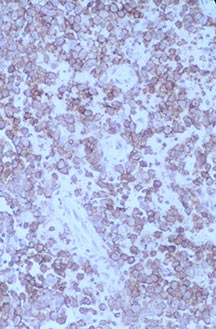

Microscopic Pathology

- Langerhans cell is diagnostic and clonal proliferation

- Nuclei show prominent nuclear groove (coffee-bean)

- Also composed of eosinophils and other inflammatory cells (non diagnostic component)

- Ratio of inflammatory cells to Langerhans cells varies

- Mitotic activity low

- Eosinophils dominate some areas forming diffuse sheets, excluding Langerhans cells

- Birbeck Granules: Electron Microscopy demonstrates granules that often take the form of a tennis raquet and form from complex invaginations of the cell membrane

- Vimentin, CD1 and S-100 positivity